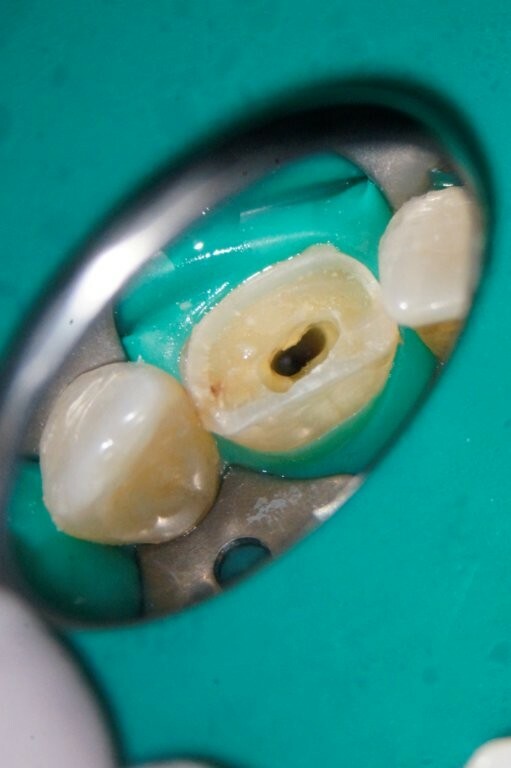

Das Zahnfragment hatte eine gute Passung auf den frakturierten Stumpf. So konnte im Vorfeld ein Silikonabdruck als Vorwall für den Kompositaufbau erstellt werden. Die endodontische Therapie sowie der Füllungsaufbau erfolgten ausschließlich unter dem hochauflösenden OP-Mikroskop (Zumax OMS2350). Die zu behandelnde Region wurde mit Ubistesin 1/200000 lokal betäubt. Anschließend wurde von 11 bis 22 ein Kofferdam angebracht. Der Zahn wurde mit einem konischen Diamanten trepaniert, die Trepanationsöffnung mit Gates-Glidden-Bohrern erweitert. Die Aufbereitung erfolgte mit dem Reciproc Blue System bis zur Größe 50.05.

Es wurde mit 15 Milliliter Natriumhypochlorid und 2,5 Milliliter EDTA gespült. Beide Flüssigkeiten wurden mittels PUI (assive Ultrasonic Irrigation) aktiviert.

Die Wurzelfüllung erfolgte in Continuus Wave Technik und Backfill in zwei Inkrementen mit

Guttapercha und AH Plus als Sealer. Anschließend wurden aufgrund der ovalen Kavität zwei Glasfaserstifte zur Stabilisation der Füllung eingebracht und mit Luxacore adhäsiv verklebt.